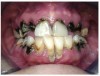

Often, the most visually striking manifestation of long-term meth use—known as “meth mouth”—is caused by the lack of saliva combined with an increase in soda drinking and extremely poor oral hygiene. This typically leads to meth abusers experiencing a large amount of caries. Decay begins with occlusal and facial caries and progresses rapidly, decaying to the bone level and often leaving only roots (Figure 1 through Figure 3).16

Fig 4 through Fig 6. Patient’s oral condition after 6 years of meth use.

The patient shown in Figure 4 through Figure 6 was a meth user for 6 years. He had a stroke at age 22. After recovering from the stroke and stabilization of his circulatory system was achieved, and once he quit using meth, he strongly desired to apply for a job and wished to improve his dental appearance. He opted to have all of his teeth extracted, as complete dentures were his only treatment option because there were no adequate abutment teeth remaining for placement of removable partial dentures.